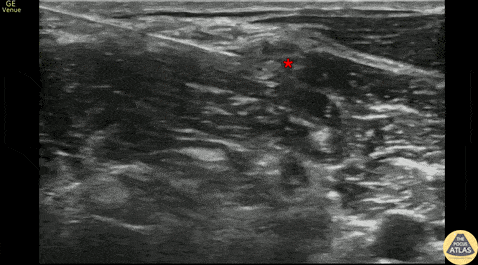

20s M with history of recurrent shoulder dislocations presented with shoulder pain and deformity after being transferred from an urgent care after multiple unsuccessful attempts at reduction using intra-articular lidocaine alone. He was neurovascularly intact and clinically dislocated, which was confirmed on US. To facilitate reduction, an interscalene brachial plexus block was performed using US guidance. Shown here, the needle enters from the posterior aspect, approaching the brachial plexus (*) and depositing anesthetic adjacent to it. The patient had relief of his pain, and closed reduction was accomplished at the bedside without need for any additional analgesia or sedation. Dr. Cheyenne Smith, PGY3 Denver Health Residency in Emergency Medicine